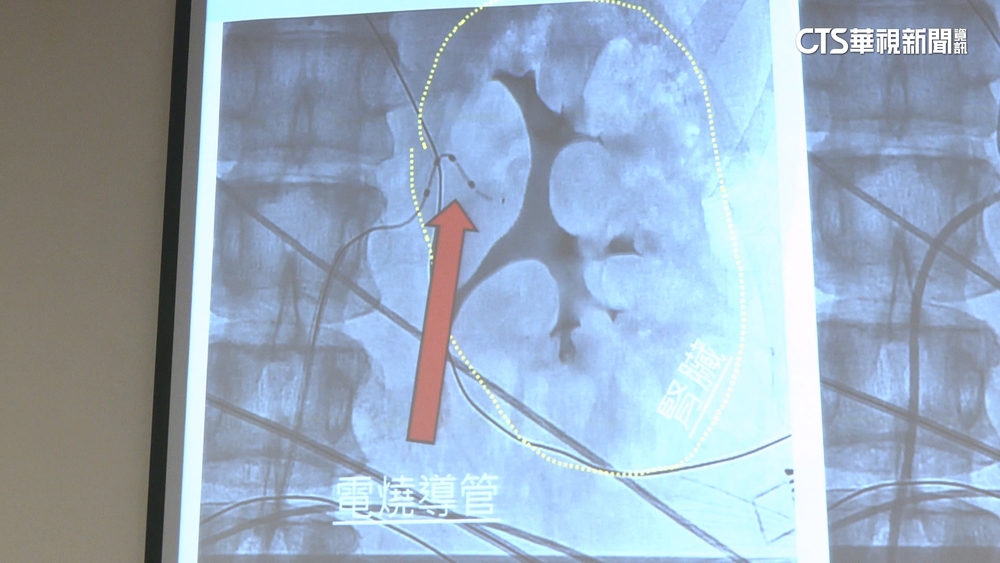

「隱性高血壓」心悸+臉潮紅 新技術3D定位!成功率高